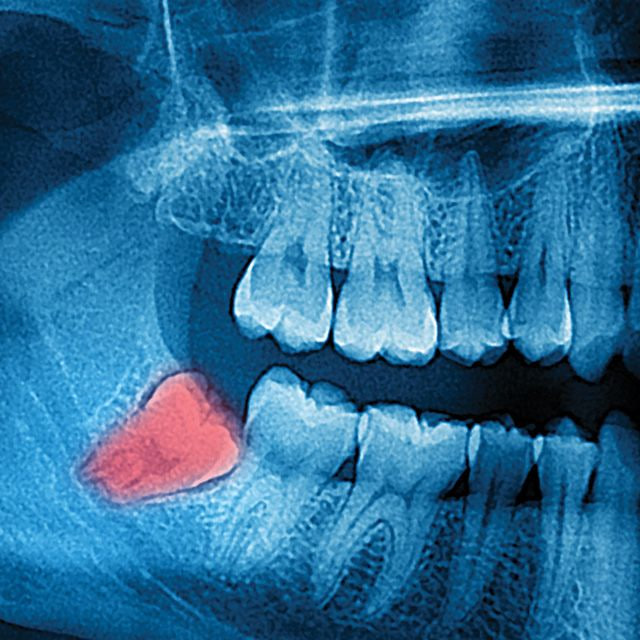

Π—ΡƒΠ±Ρ‹ мудрости ΠΎΠ±Ρ‹Ρ‡Π½ΠΎ Π²ΠΎΡΠΏΡ€ΠΈΠ½ΠΈΠΌΠ°ΡŽΡ‚ΡΡ ΠΊΠ°ΠΊ ΠΏΡ€ΠΎΠ±Π»Π΅ΠΌΠ°: болят, Π²ΠΎΡΠΏΠ°Π»ΡΡŽΡ‚ΡΡ, растут ΠΊΡ€ΠΈΠ²ΠΎ ΠΈ Ρ‡Π°Ρ‰Π΅ всСго Ρ‚Ρ€Π΅Π±ΡƒΡŽΡ‚ удалСния.

Но Ρƒ этой истории Π½Π΅ΠΎΠΆΠΈΠ΄Π°Π½Π½ΠΎ появился Π²Ρ‚ΠΎΡ€ΠΎΠΉ ΡΡŽΠΆΠ΅Ρ‚: Π²Π½ΡƒΡ‚Ρ€ΠΈ Π·ΡƒΠ±Π° Π΅ΡΡ‚ΡŒ Ρ‚ΠΊΠ°Π½ΡŒ (ΠΏΡƒΠ»ΡŒΠΏΠ°), Π² ΠΊΠΎΡ‚ΠΎΡ€ΠΎΠΉ находятся стволовыС ΠΊΠ»Π΅Ρ‚ΠΊΠΈ.

Π‘Ρ‚Π²ΠΎΠ»ΠΎΠ²Ρ‹Π΅ ΠΊΠ»Π΅Ρ‚ΠΊΠΈ - это ΠΊΠ»Π΅Ρ‚ΠΊΠΈ с особой ΡΠΏΠΎΡΠΎΠ±Π½ΠΎΡΡ‚ΡŒΡŽ: ΠΎΠ½ΠΈ ΠΌΠΎΠ³ΡƒΡ‚ ΠΏΡ€Π΅Π²Ρ€Π°Ρ‰Π°Ρ‚ΡŒΡΡ Π² Π΄Ρ€ΡƒΠ³ΠΈΠ΅ Ρ‚ΠΈΠΏΡ‹ ΠΊΠ»Π΅Ρ‚ΠΎΠΊ. НапримСр, Π² костныС, хрящСвыС ΠΈ, ΠΊΠ°ΠΊ ΠΏΠΎΠΊΠ°Π·Ρ‹Π²Π°ΡŽΡ‚ исслСдования, Π² ΠΊΠ»Π΅Ρ‚ΠΊΠΈ, ΠΏΠΎΡ…ΠΎΠΆΠΈΠ΅ Π½Π° Π½Π΅Ρ€Π²Π½Ρ‹Π΅.

Π˜ΡΡΠ»Π΅Π΄ΠΎΠ²Π°Ρ‚Π΅Π»ΠΈ ΠΏΠΎΠΊΠ°Π·Π°Π»ΠΈ: стволовыС ΠΊΠ»Π΅Ρ‚ΠΊΠΈ ΠΈΠ· ΠΏΡƒΠ»ΡŒΠΏΡ‹ Π·ΡƒΠ±Π° ΠΌΠΎΠ³ΡƒΡ‚ ΠΏΡ€Π΅Π²Ρ€Π°Ρ‰Π°Ρ‚ΡŒΡΡ Π² Π½Π΅ΠΉΡ€ΠΎΠ½ΠΎΠΏΠΎΠ΄ΠΎΠ±Π½Ρ‹Π΅ ΠΊΠ»Π΅Ρ‚ΠΊΠΈ, ΠΈ Π³Π»Π°Π²Π½ΠΎΠ΅, это Π½Π΅ просто внСшнСС сходство!